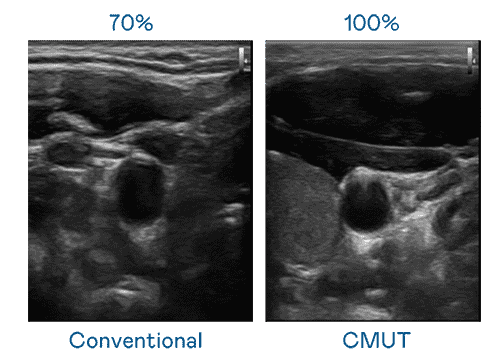

CMUT 技术是一种用电容式微机电元件来产生超音波讯号的技术。。。与传统 PZT 压电式技术相比,,,,CMUT 频宽增加 30%,,,,更宽频的超音波讯号让影像解析度大幅提升,,是实现高影像品质医疗超音波扫描、、促进精准医疗发展的关键技术。。

超音波影像的解析度高低,,首先取决于探头能发出的讯号频宽。。彩霸王 CMUT 可提供高清晰的超音波讯号,,,提供高频宽、、、、高灵敏度、、影像纹理细节更高的超音波影像,,协助医护人员缩短影像判读时间及利用精准的医疗影像进行诊断。。